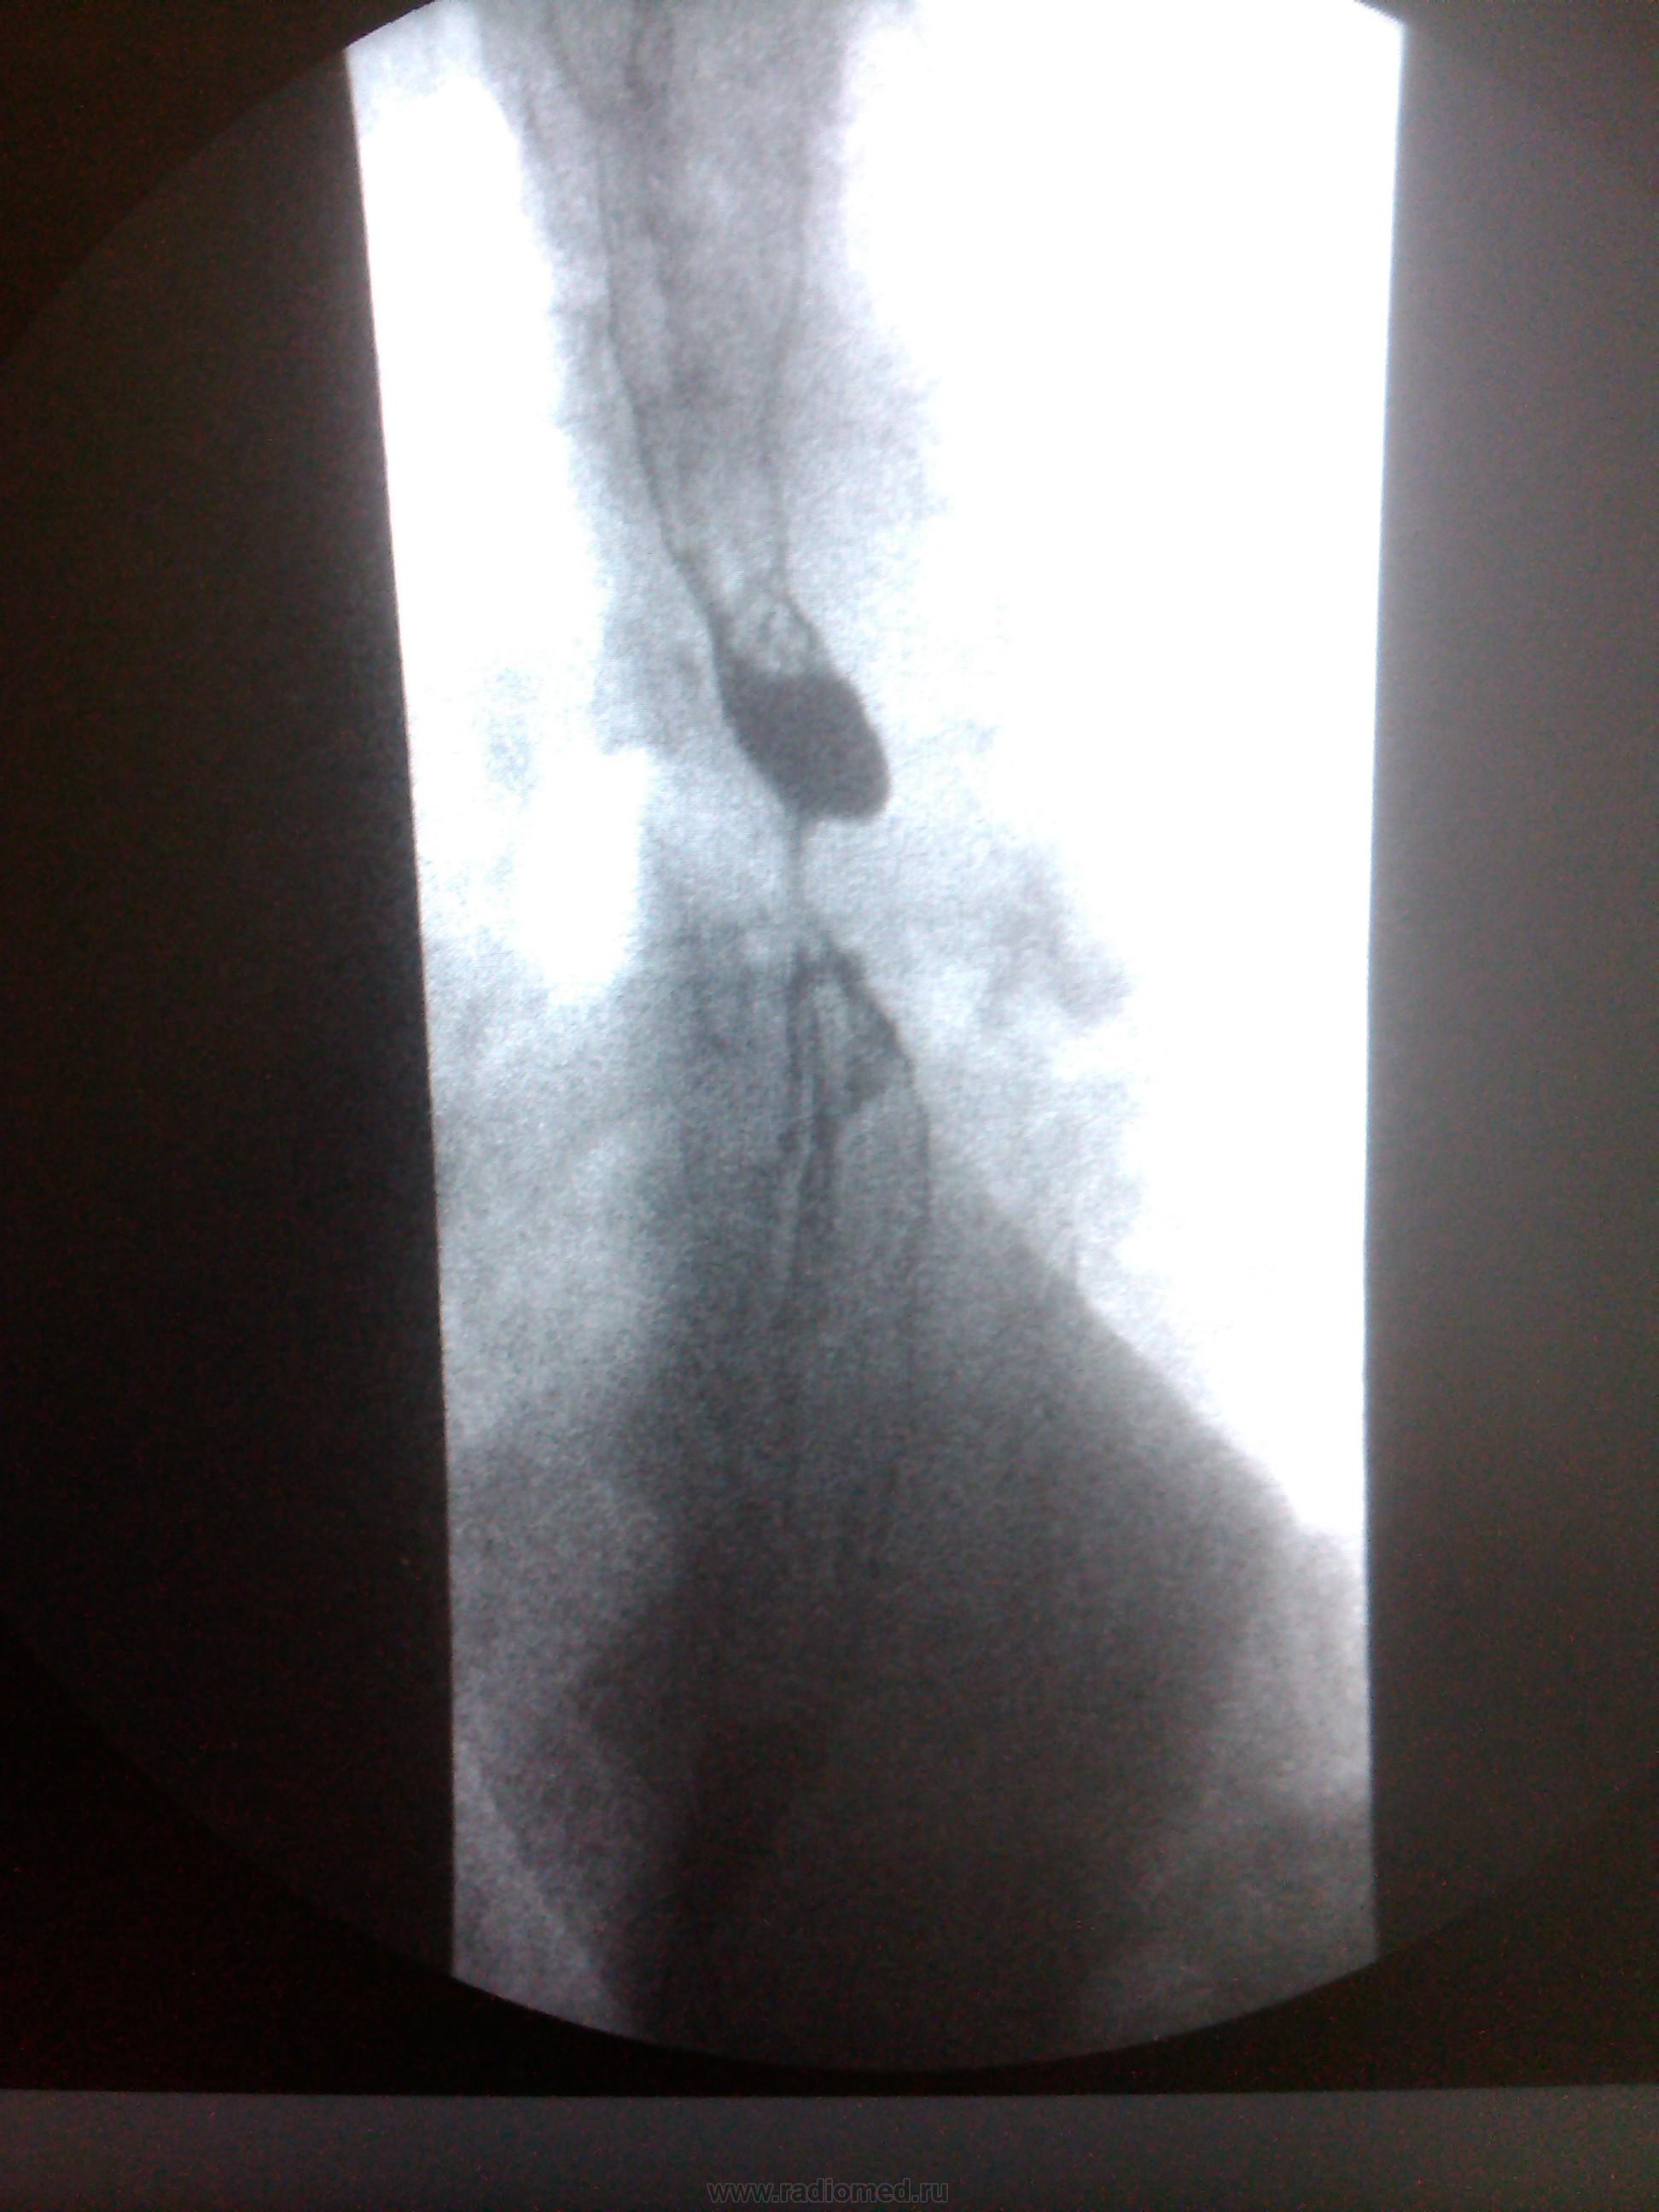

Пациентка, 74 года. Операция по поводу дивертикула пищевода лет 25 назад. Нужны мнения!

Ахалазия кардии, скользящая грыжа пищеводного отверстия диафрагмы, мелкий дивертикул с/3 пищевода - это мнение.

Тракционный дивертикул пищевода. ГПОД. Эзофагоспазм. За ахалазию сомнительно. А вот почему пищевод такой широкий - стоит задуматься.

Может быть он гипотоничный + третичные сокращения вот и выглядит широким, возможно там и эзофагит.

Я такие широкие пищеводы вижу регулярно при склеродермии, например. И клиницисты как бы должны знать о ее существовании, например же. Наше дело - констатировать факты, а их интерпритацию стоит все же оставить другим докторам.

"Нужны мнения!" Мнение: плохо оперировали тогда или: не причину, а следствие. Дивертикул есть и лит есть. ИМХО. А где причина - коллеги по поводу дистального отдела отд. пищевода  уже писали. Теоретически - проблема с 12п. кишкой( по Витебскому)